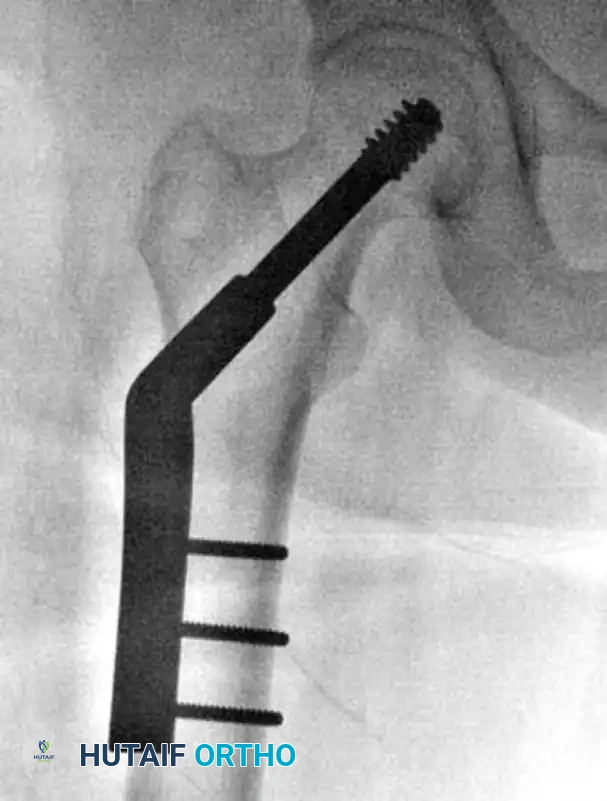

1. Guide Pin Insertion

- Place a 135-degree angled guide against the lateral femoral cortex.

- Insert a 2.8-mm threaded guide pin through the guide, aiming for the exact center of the femoral head on both the AP and lateral fluoroscopic views (the "center-center" position).

- To assist with anteversion alignment, a secondary guide pin can be placed anteriorly along the femoral neck.

- Advance the primary guide pin until its tip is approximately 5 mm from the subchondral bone of the articular surface.

4. Plate Application

- Slide the side plate over the lag screw shaft and advance it onto the lateral aspect of the femur.

- Use a tamp to fully seat the plate barrel over the screw and flush against the lateral cortex.

- Remove the lag screw retaining rod, the insertion wrench, and finally, the guide pin.

5. Cortical Fixation and Compression

- Secure the side plate to the femoral shaft using a bone clamp.

- Drill, measure, tap (if necessary), and place two to four bicortical 4.5-mm cortical screws through the plate into the femoral shaft. If a screw was initially used to pull the plate to the bone, it may need to be exchanged for a shorter one once the plate is fully seated.

- Release the traction on the fracture table.

- If additional impaction is desired, insert a compression screw into the back of the lag screw. Alternatively, manual compression can be applied by gently pushing the leg proximally.

The Tip-Apex Distance (TAD)

Proper placement of the lag screw is the single most important surgeon-controlled variable in reducing the incidence of implant failure, specifically lag screw "cut-out" through the superior femoral head.

The Tip-Apex Distance (TAD), described by Baumgaertner, is calculated by summing the distance from the tip of the lag screw to the apex of the femoral head on both the AP and lateral radiographs, corrected for magnification.

* Rule of Thumb: As the TAD increases above 25 mm, the risk of biomechanical failure and cut-out increases exponentially. A center-center position inherently minimizes the TAD.